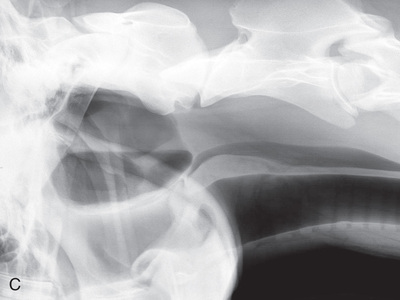

| Cervical spine | Lateral (Fig. 24.58) | Side of the cervical region. | Opposite side of neck. | Centered on region of choice: | Because of the size of the patient, the cervical spine must be exposed in three views. The patient can be standing or recumbent. |